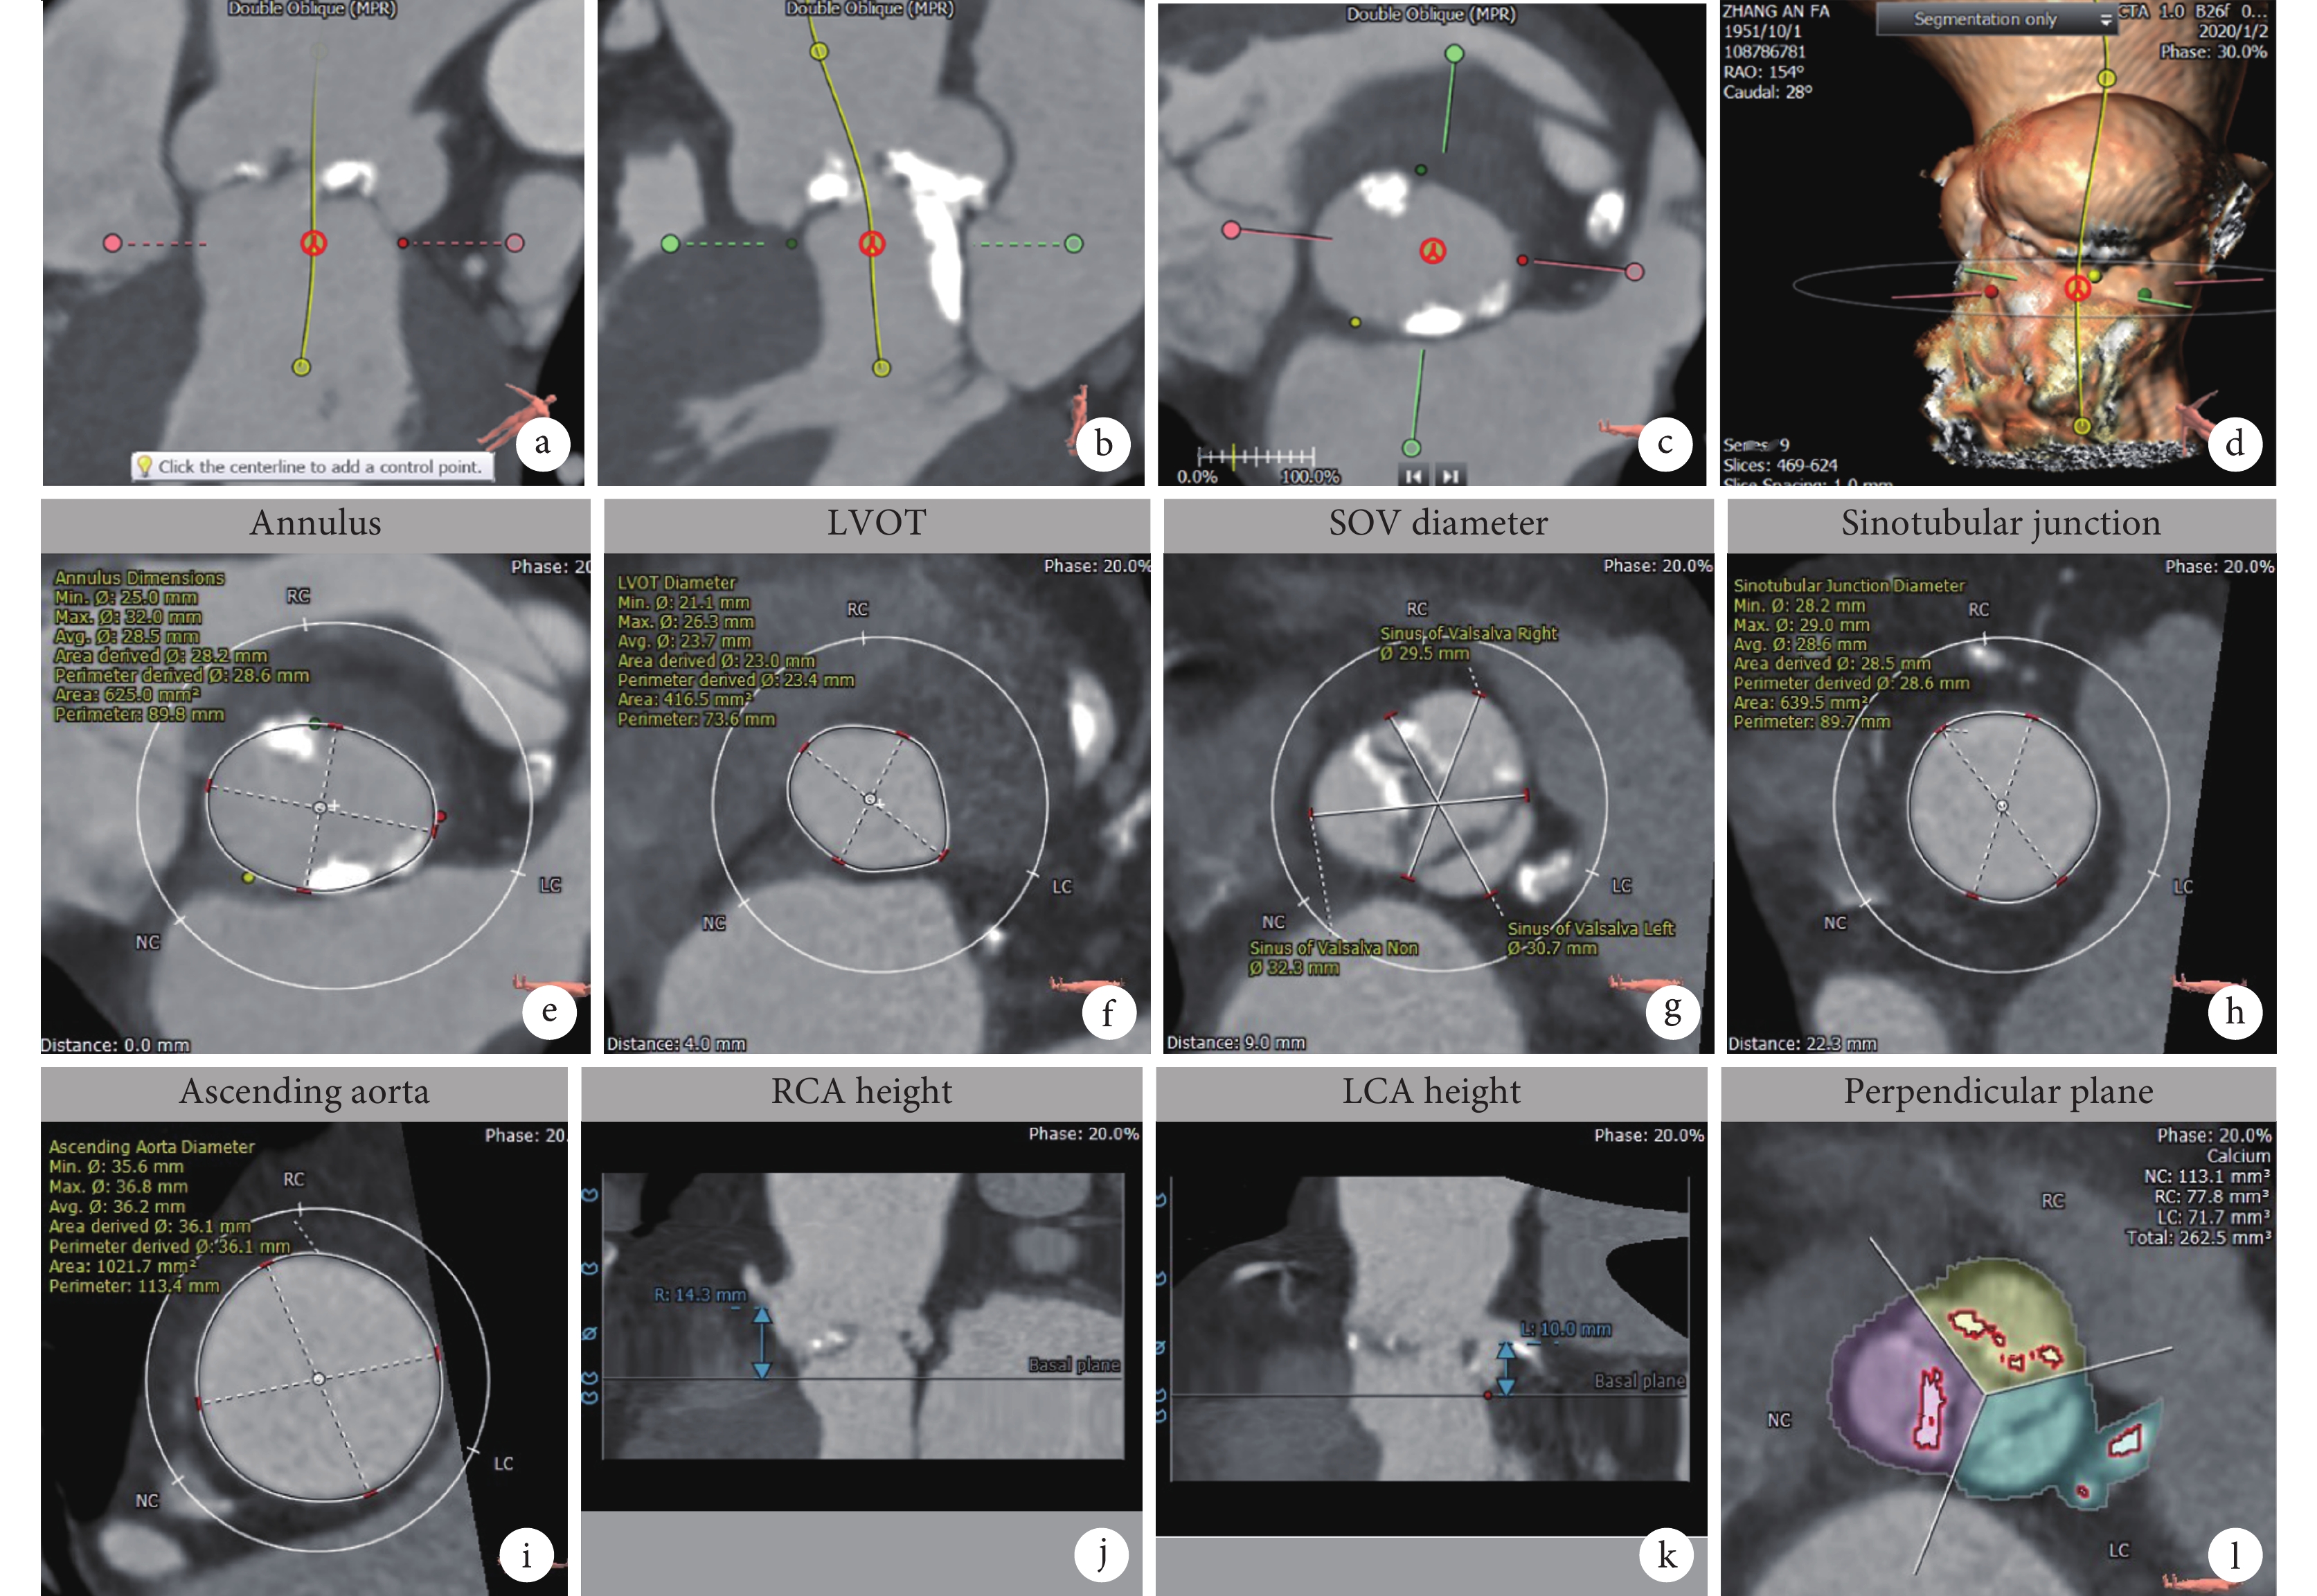

術前對主動脈瓣根部進行分析評估,選擇收縮期的最佳圖像(約30%的圖像),首先確定瓣環平面,測量主動脈瓣環的直徑、面積和周長。在瓣環平面的基礎上再進行主動脈根部其他解剖的測量,主動脈根部測量內容[14]包括:瓣環平面直徑、面積、周長,LVOT直徑、面積、周長,瓦氏竇直徑,竇部高度,左右冠脈高度,竇管交界直徑、面積和周長,升主動脈直徑,自體瓣葉高度測量,鈣化分布和鈣化積分(圖4)。

a~d:瓣環平面確定;e~k:主動脈根部相關測量;l:鈣化積分評估